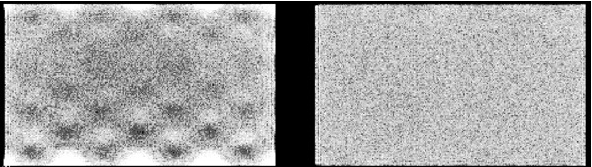

Figure 1:Image of a uniform phantom. E = energy correction, L = linearity correction, U = uniformity correction.

Figure 1 shows the influence of the corrections on the image of a uniform phantom. Without any correction, the photomultipliers are clearly visible as spots of increased intensity. After energy correction this is still the case, but the response of the PMTs is more uniform. When in addition linearity correction is applied, the image is uniform, except for Poisson noise. Uniformity correction produces a marginal improvement which is hardly visible.